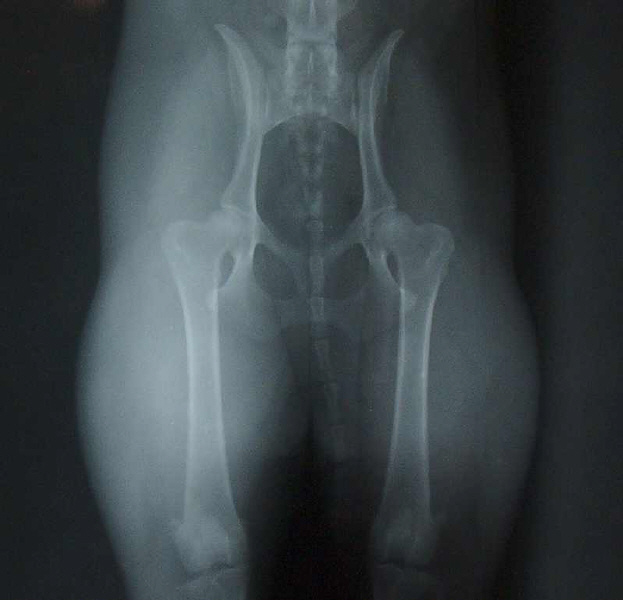

HD-Röntgenuntersuchung

Von Jamilah's Hüftgelenken wurden zwei Röntgenaufnahmen erstellt.

Sinn der Untersuchung ist es, auszuschließen, dass Jamilah eine vererbliche Hüftgelenks-Dysplasie hat. Um die geforderten Aufnahmen erstellen zu können war es notwendig, Jamilah in eine Narkose zu versetzen.

Gemäß der Zuchtordnung des BKD wurde eine Aufnahme in gestreckter und eine in gebäugter Haltung erstellt.

Gestreckte Haltung